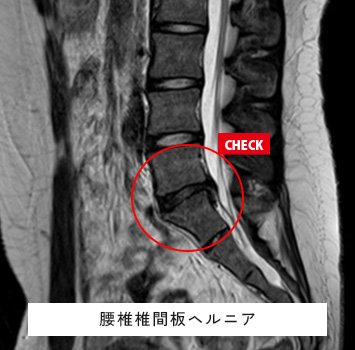

腰椎MRIチェック

このような方におすすめします。

• 慢性的に腰が痛い、重い

• おしり〜太もも、足に痛みやしびれがある

• ヘルニアや加齢による変化(変形性腰椎症)、ぎっくり腰が心配

• 尻もちをついた、スポーツや仕事で腰に負担がかかった後の腰痛

筋肉と関節痛みのMRIチェック名古屋なら

レントゲン検査では分からない椎間板、筋肉、靱帯などの様子が

がたった10分の検査で評価出来ます!

腰下肢痛、レントゲンで異常なし

スポーツを続けており強い腰痛、レントゲンで異常なし

料金:¥17,600(税込)

ご予約はこちら

腰椎椎間板ヘルニア、腰部脊柱管狭窄症、変形性腰椎症、腰椎分離・すべり症、脊椎腫瘍、脊椎炎・化膿性脊椎炎、椎体骨折、脊髄空洞症、脊髄・馬尾神経の炎症性疾患(多発性硬化症など)、関節リウマチなどの炎症性疾患 など